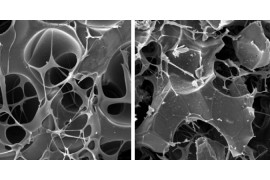

El virus de la COVID-19 manipula el ARN de la célula huésped para desactivar el sistema inmunitario

Un estudio de la Universidad Federal de São Paulo describe cómo el SARS-CoV-2 interactúa de manera inédita con el ARN de las células pulmonares infectadas; los resultados pueden orientar la búsqueda de nuevos tratamientos y vacunas